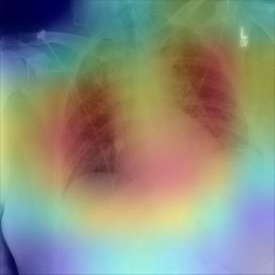

The COVID-19 disease was first discovered in Wuhan, China, and spread quickly worldwide. After the COVID-19 pandemic, many researchers have begun to identify a way to diagnose the COVID-19 using chest X-ray images. The early diagnosis of this disease can significantly impact the treatment process. In this article, we propose a new technique that is faster and more accurate than the other methods reported in the literature. The proposed method uses a combination of DenseNet169 and MobileNet Deep Neural Networks to extract the features of the patient's X-ray images. Using the univariate feature selection algorithm, we refined the features for the most important ones. Then we applied the selected features as input to the LightGBM (Light Gradient Boosting Machine) algorithm for classification. To assess the effectiveness of the proposed method, the ChestX-ray8 dataset, which includes 1125 X-ray images of the patient's chest, was used. The proposed method achieved 98.54% and 91.11% accuracies in the two-class (COVID-19, Healthy) and multi-class (COVID-19, Healthy, Pneumonia) classification problems, respectively. It is worth mentioning that we have used Gradient-weighted Class Activation Mapping (Grad-CAM) for further analysis.